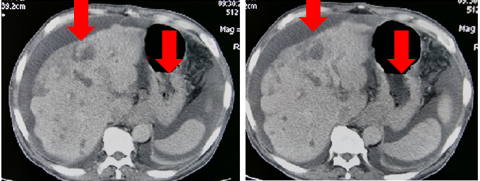

2018-11-05加入S1单药化疗,6次靶向+2周期S1化疗后,肿瘤标记物下降:CEA 947ug/L → 23.5ug/L血常规恢复正常。肿瘤明显缩小,范围变少。ECOG 1分

图3

病灶缩小,疗效评价:PR